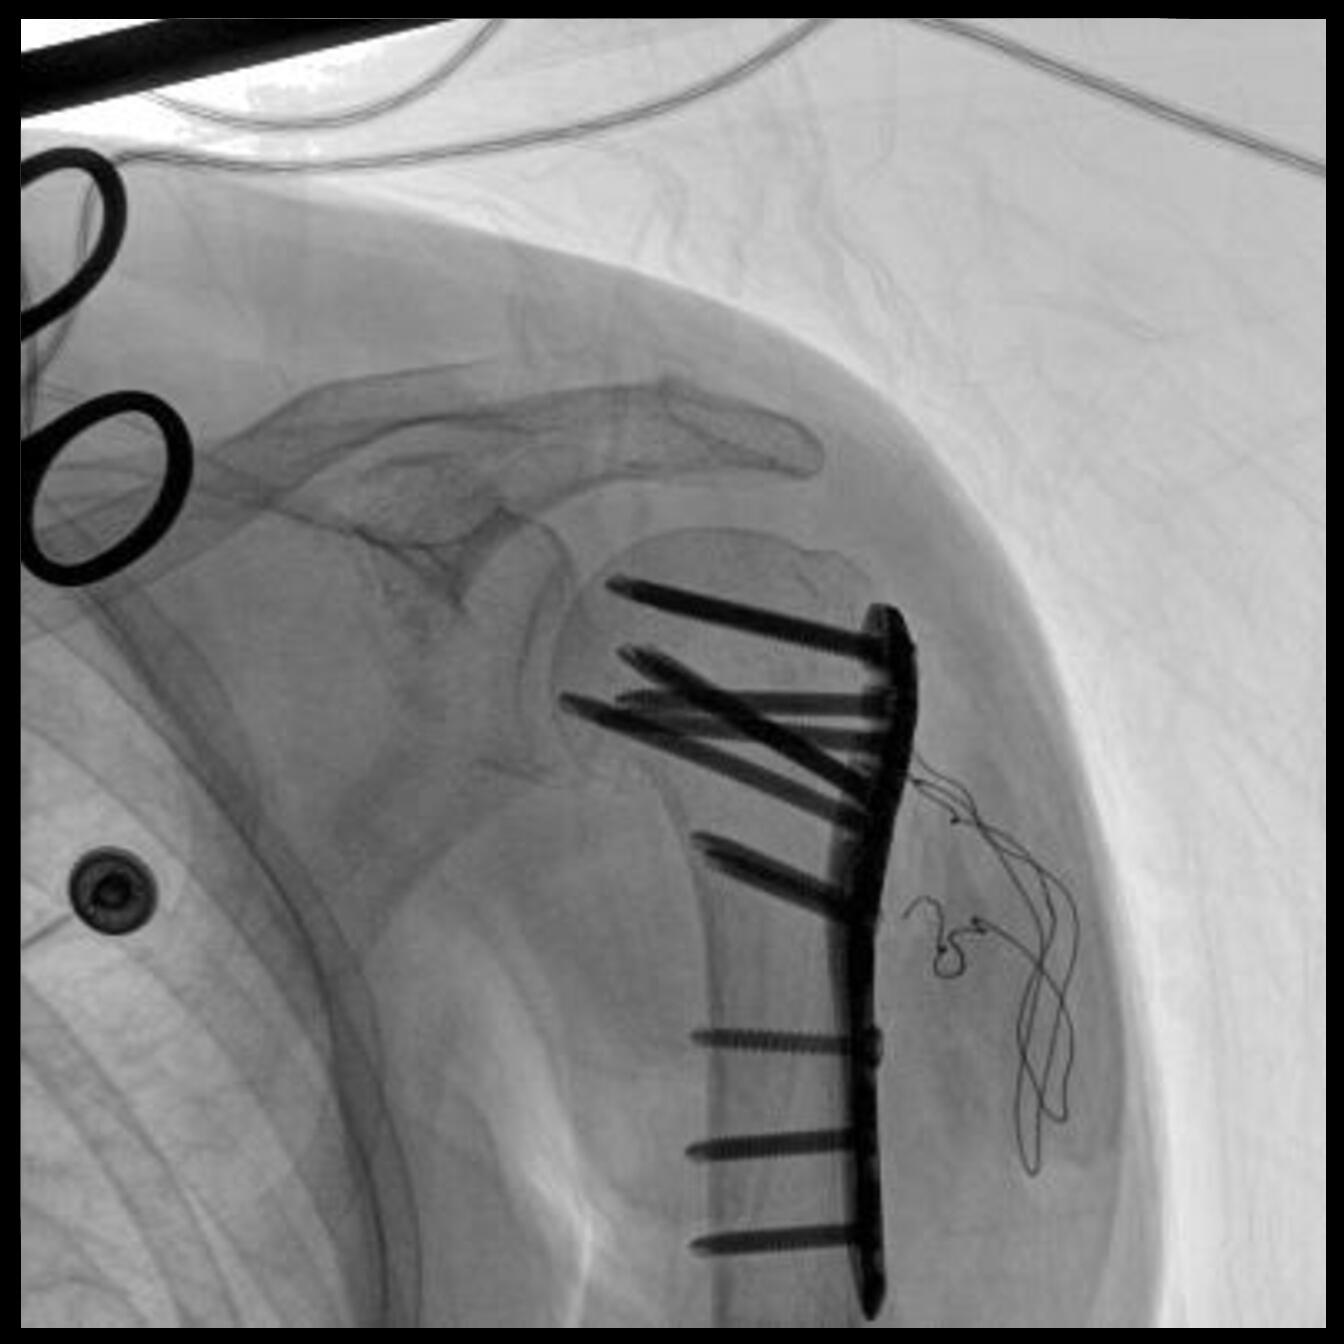

Clinical picture

臨床圖片